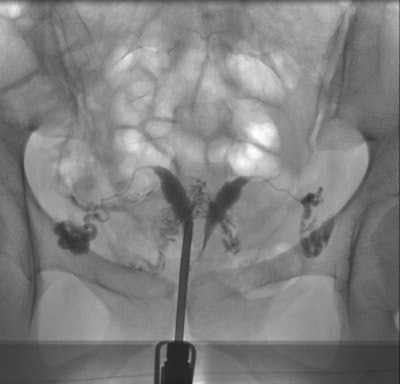

Of all the HSG exams, 226 (55%) were normal, 94 (23%) showed minor abnormalities, and five (1.2%) were not diagnostic. Eighty-six (21%) examinations were pathological. Twenty-nine patients underwent subsequent laparoscopy -- proximal tubal occlusion diagnosed at HSG was ruled out in nine of 23 cases. Follow-up information was unavailable for 20 patients. Nineteen of 66 patients with follow-up after pathological HSG had at least one subsequent successful pregnancy, while 41 patients had no further treatment and no pregnancies.

"The relatively low percentage (21%) of pathological exams in our population underlines the need for good patient preselection," they wrote. "The high false-positive rate for proximal tubal occlusion (39%), probably due to tubal spasm, demonstrates the importance of antiperistaltic agents and delayed imaging."

There was a high pregnancy rate in patients with pathological HSG -- most were spontaneous without tubal or uterine surgery.

"This could mean that the indication for HSG was too broad or that there could even be a therapeutic effect of the HSG procedure, i.e., improved patency of the fallopian tube because of the flushing during the examination," they wrote.